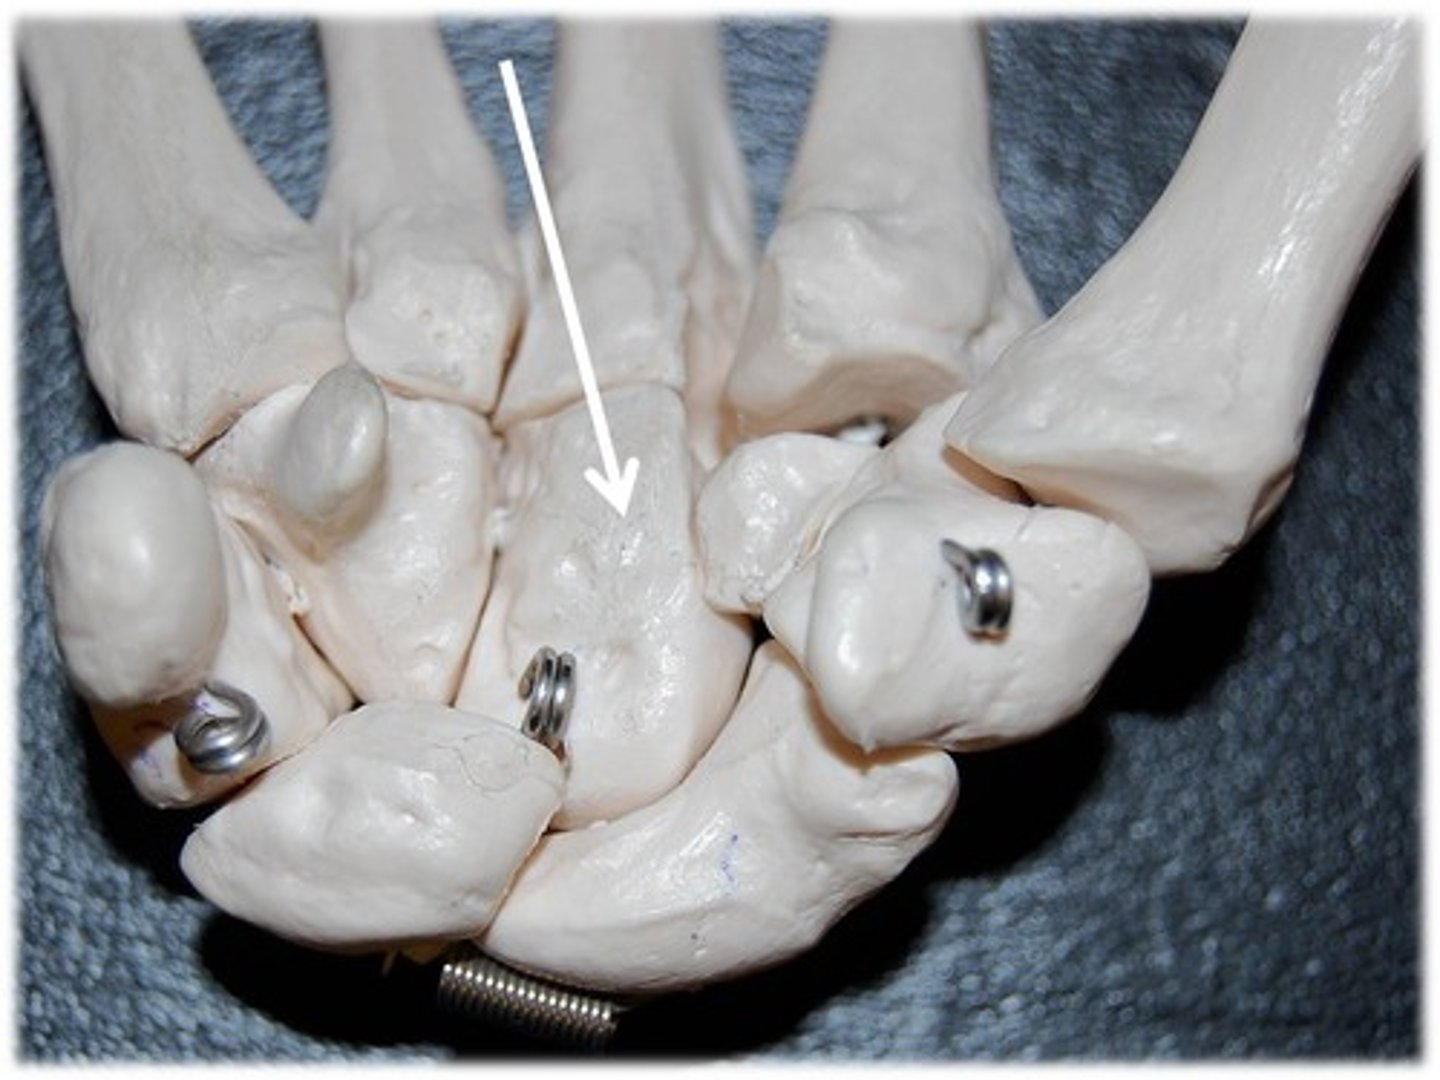

metacarpals

carpals

ID group

metacarpals

ID bone group

carpals

ID bone group

phalanges

ID bone group

scaphoid

ID bone

trapezium

ID bone

metacarpal

ID YELLOW bones

carpals

ID PURPLE bones

lunate

ID specific bone

scaphoid

ID specific bone

pisiform

ID specific bone

triquetrum

ID specific bone

trapezium

ID specific bone

capitate

ID specific bone

hamate

ID specific bone